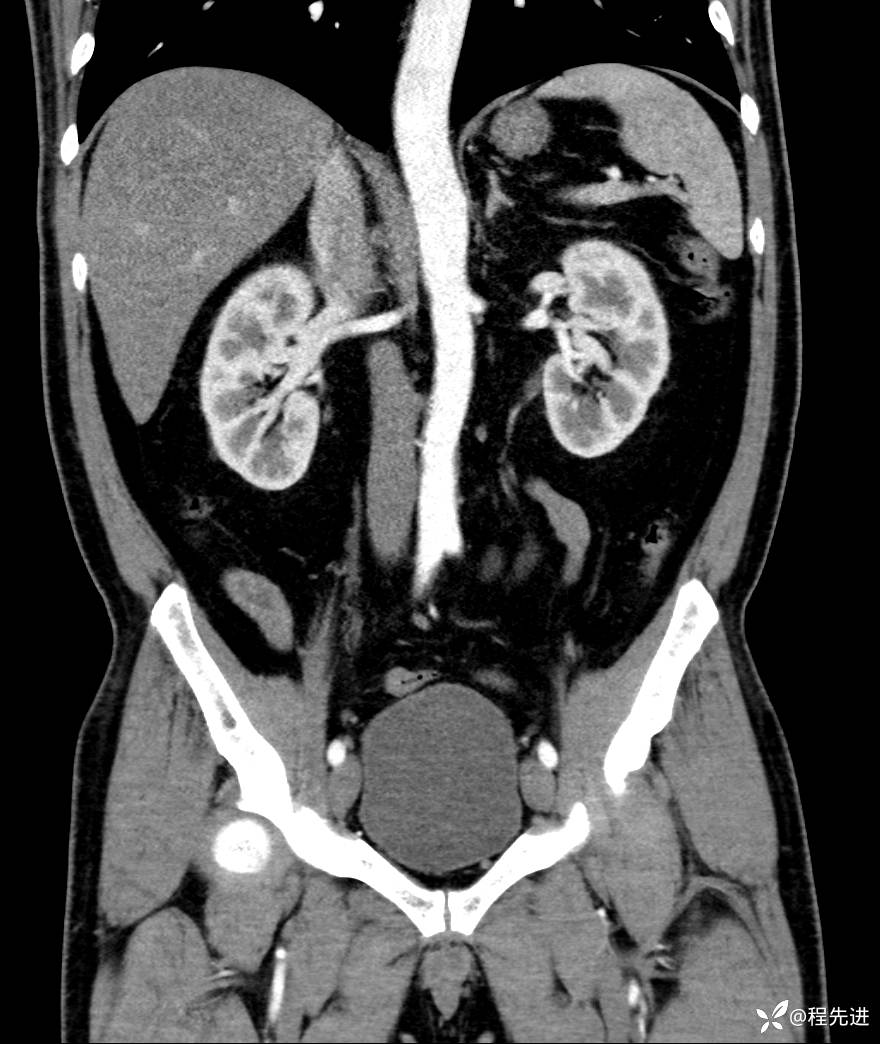

【腹盆】特别精彩病例|发现腹膜后肿物1月余

患者性别:男

患者年龄:42岁

主诉:发现腹膜后肿物1月余

现病史:患者1月余前查体,行超声检查提示:后腹膜囊实性肿块;慢性胆囊炎伴胆囊内结石;无腹痛腹胀,不伴腹泻发热等;偶感腰背部酸痛。

CT平扫+增强: